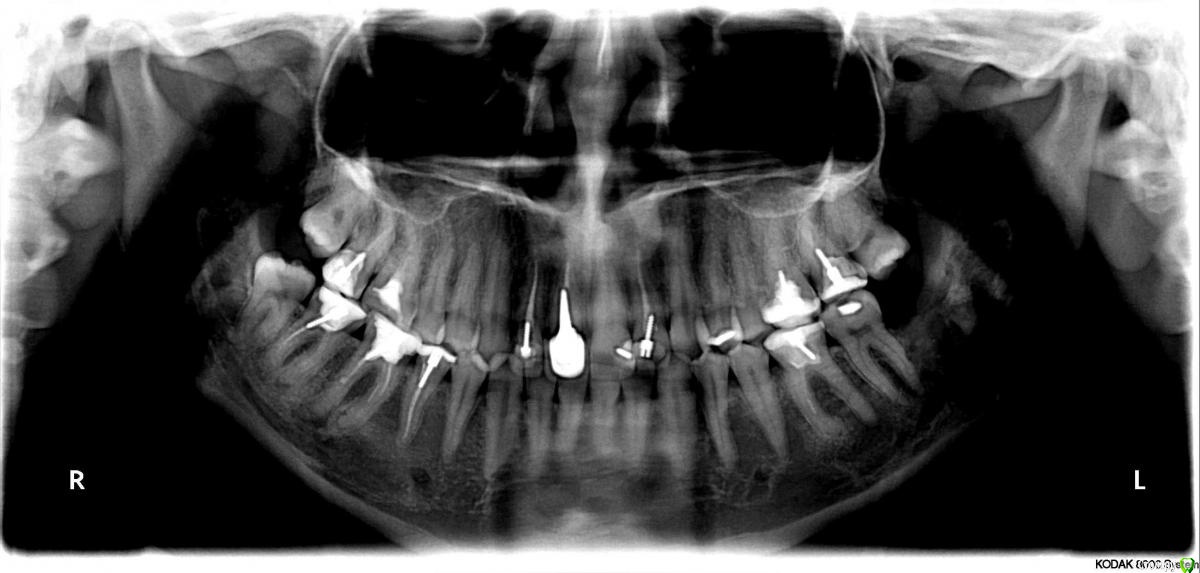

Ника9115 Опубликовано 29 марта, 2017 Автор Поделиться Опубликовано 29 марта, 2017 Cделала снимок, хотела бы еще спросить по поводу других зубов, стоит ли удалять 8 ? Да и другие зубы интересуют, хотелось бы все пролечить перед планированием . Ссылка на комментарий

red_butler Опубликовано 29 марта, 2017 Поделиться Опубликовано 29 марта, 2017 Все восьмерки удаляйте. Работы во рту предстоит много... Ссылка на комментарий